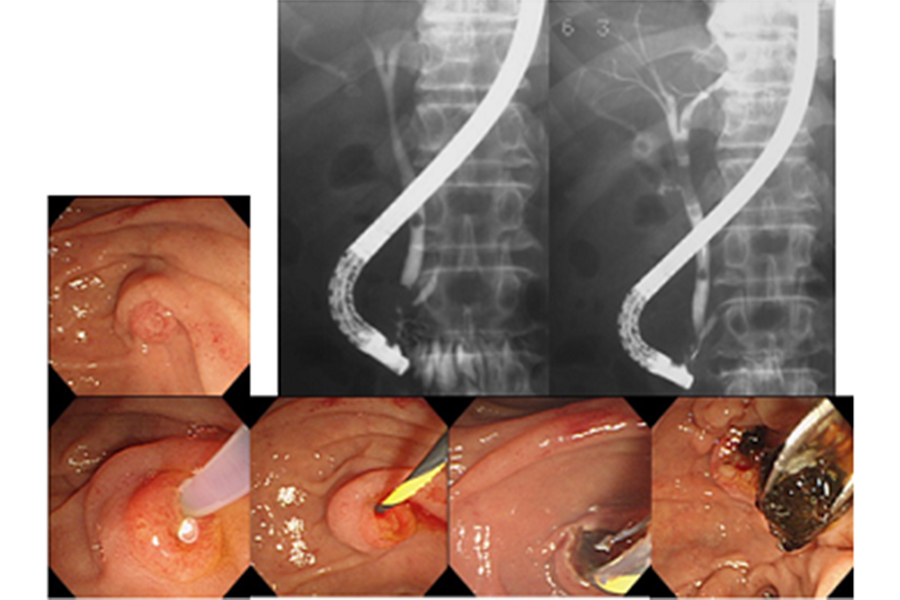

内視鏡的逆行性胆道膵管造影(ERCP)は、内視鏡を口から入れて十二指腸まで進め、胆管や膵管にカテーテルを挿入して造影剤を注入し、胆道・膵管のレントゲン撮影を行う検査です(図1)。

これにより結石や腫瘍といった胆管や胆嚢、膵管の異常を詳しく調べることができます。近年では画像診断の進歩により、超音波検査やCT、MRIでも胆道や膵管の情報が得られるようになってきていますが、悪性の病気が疑われた場合にはERCP実施時に胆道や膵管の細胞や組織を採取して病理検査を行うことがあります。また、胆管・膵管の狭窄に対してプラスチックや金属のステント(筒状のもの)を挿入して、胆汁や膵液の流出障害を改善させる治療を行うことがあるほか(図2)、胆管結石や膵石に対しては内視鏡で取り除く治療も行うことができます(図3)。このようにERCPは胆膵領域の診断、治療に重要な役割を担っています。